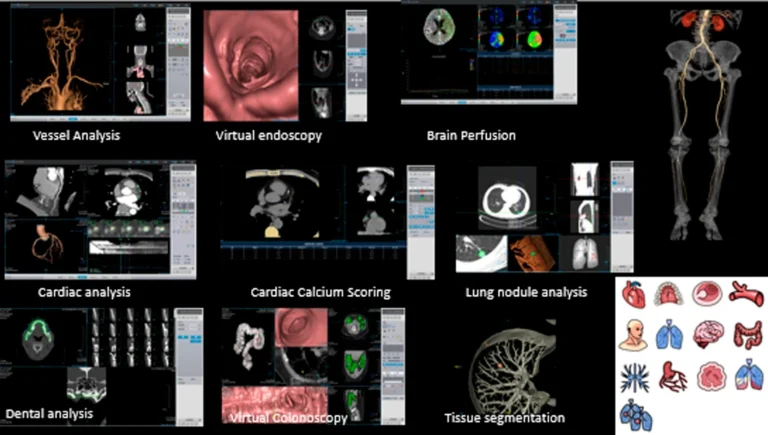

• Vollumfängliche klinische Diagnoseplattform.

• Der voll ausgestattete 128-Zeilen-CT-Scanner kann

allgemeine Läsionen sowohl qualitativ als auch quantitativ genau lokalisieren und diagnostizieren und bietet mit einer umweltfreundlichen Plattform mit ultraniedriger Strahlendosis

einen umfassenden klinischen Nutzen,

einschließlich zahlreicher kardiologischer Anwendungen .